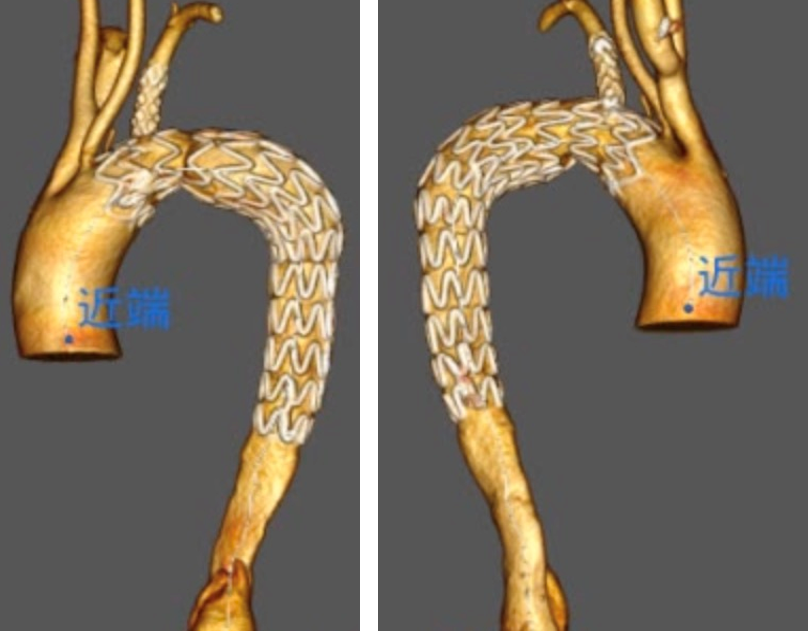

(术后30天CTA显示,主体、分支、迷走动脉均通畅,弓上迷走动脉成功保留)